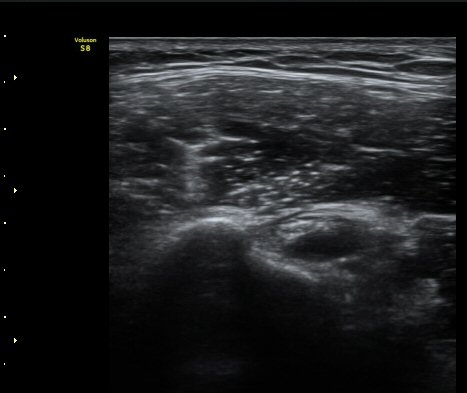

¼ºº° / ³ªÀÌ

¿©ÀÚ/ 50¼¼

ÁÖÁõ»ó

³Ñ¾îÁø ÈÄ ½ÉÇØÁö´Â ¾î±úÀÇ ÅëÁõ°ú °­Á÷

º´·Â

³Ñ¾îÁø ÈÄ ¾î±úÀÇ ÅëÁõÀÌ ¹ß»ýÇÏ¿© Ÿ º´¿ø ³»¿øÇÏ¿© ¿¢½º·¹ÀÌ °Ë»ç¿¡¼­ ƯÀÌ ¼Ò°ß ¾ø´Ù´Â ¼Ò°ßÀ» µè°í Áö³ÁÀ¸³ª ¾î±úÀÇ ÅëÁõÀÌ ½ÉÇØÁö°í Á¡Á¡ ¾î±ú°¡ ±»¾îÁ® ³»¿ø

ÃÊÀ½ÆÄ °Ë»ç